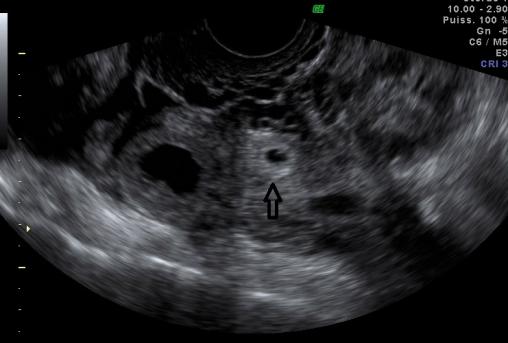

Sac gestationnel extra-utérin

Image en cocarde (flèche) du sac gestationnel extra-utérin, proche de l’ovaire droit.